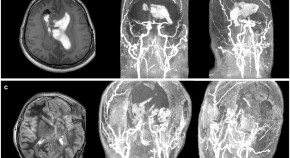

Dolichoectasia is a condition that causes dilatation and/or tortuosity of both intracranial and extracranial arteries. Intracranial dolichoectasia can be asymptomatic or manifest with compressive and/or vascular symptoms, such as cranial neuropathies or hemorrhagic stroke. In this article, Gutierrez et al. provide a review of the existing dolichoectasia literature and identify gaps in our knowledge to aid future research.